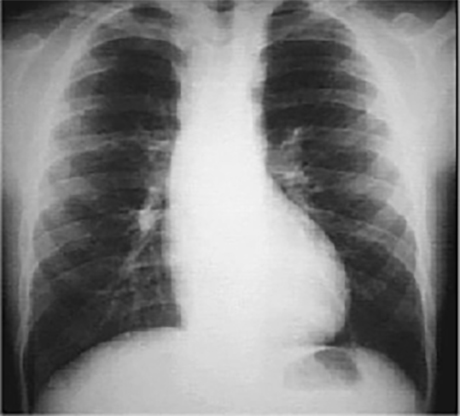

This chest X ray shows rib notching. In this PA view, it is demonstrated by a scalloped or notched appearance of the inferior rib margin, especially well seen in the posterior fourth to seventh ribs.

This is typically seen in patients with coarctation of the aorta, where collateral circulation in the intercostal arteries causes them to become large and tortuous and erode the adjacent rib margin.